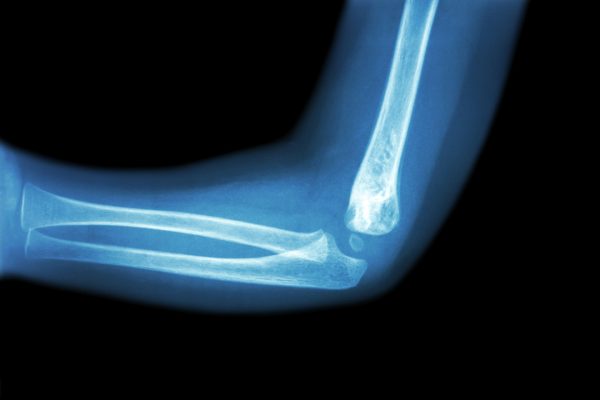

Este é um recurso que está disponível oferecido em formato JPG. Este é um dos formatos de imagem mais utilizados no mundo, conhecido por sua alta compatibilidade e qualidade visual, ideal para projetos digitais e impressos. O arquivo possui tamanho de 3.13 MB e está disponível sob a licença Grátis. Esta licença permite o uso do recurso tanto em projetos pessoais quanto comerciais.